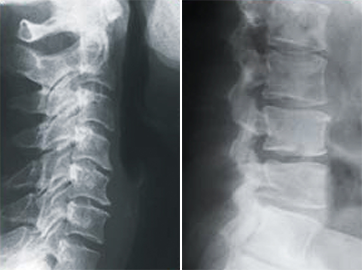

image

第3段階

• 重度の関節面や椎骨の変性(癒合)

• 神経組織の萎縮

• 重度の可動域制限

• 神経組織の委縮